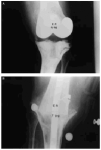

En nueve pacientes, el fracaso de la artroplastia se debió a la infección profunda (Fig. 2), aislando gérmenes del género Staphylococcus en siete de ellos. De los nueve pacientes restantes, en ocho el fracaso de la artroplastia fue debido a un aflojamiento aséptico (Fig. 3) y el caso restante fue causado por una artrofibrosis.

Figura 3. Fracaso aséptico artroplastia de rodilla. A: Radiografía preoperatoria, inestabilidad grave en descarga. B: Artrodesis.